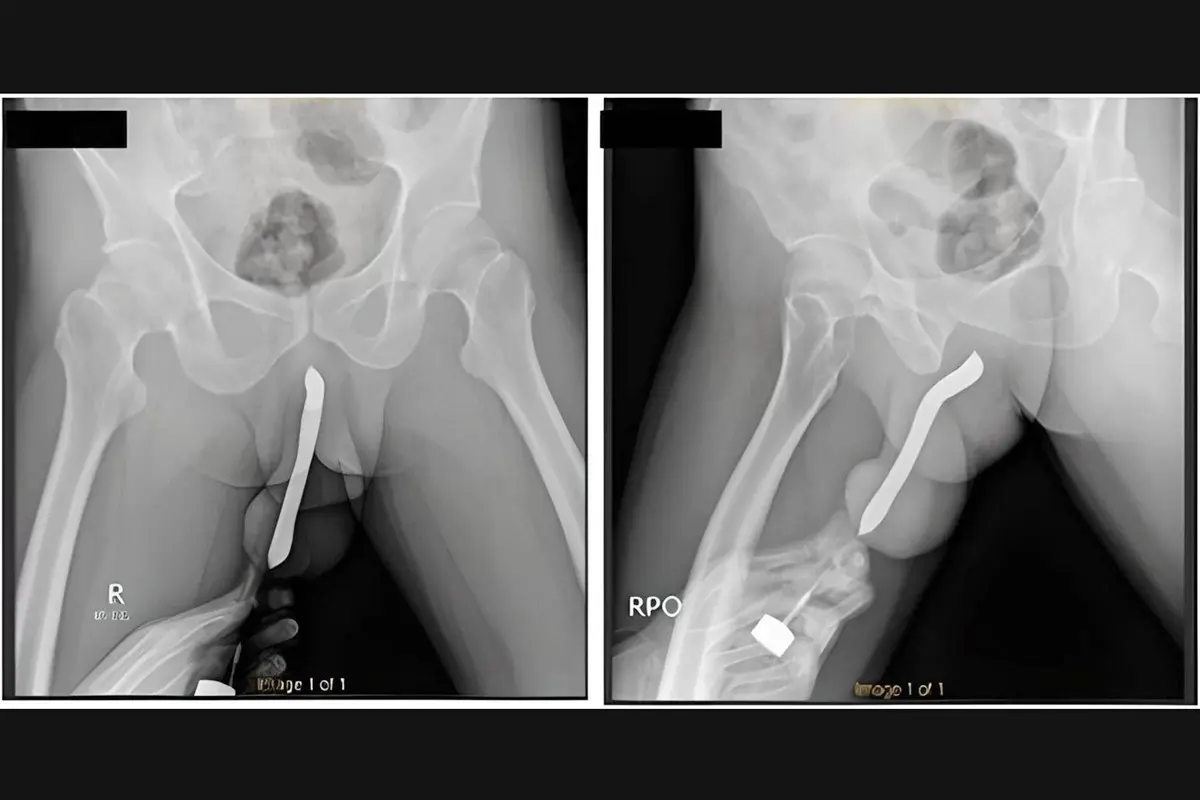

Um homem de 43 anos, da Indonésia, precisou passar por uma cirurgia após uma escova de dentes quebrar dentro do pênis dele durante uma relação sexual. O objeto foi inserido no órgão sexual pelo próprio paciente.

Os médicos do Hospital Geral Acadêmico Soetomo, na cidade de Surabaya, contam que o homem esperou 12 horas para procurar atendimento médico. Ao chegar ao pronto-socorro, o pênis dele estava muito inchado e disforme.

Ele admitiu para os socorristas que enfiou a escova de dentes no órgão sexual para “satisfação pessoal”. Também acrescentou que já havia feito um pequeno corte no órgão para conseguir inserir objetos no local com mais facilidade.

O indonésio passou por uma cirurgia de duas horas e recebeu alta três dias depois. Na consulta de retorno, um mês depois, ele disse não ter sofrido complicações e conseguir urinar normalmente. O pênis também voltou ao formato original.